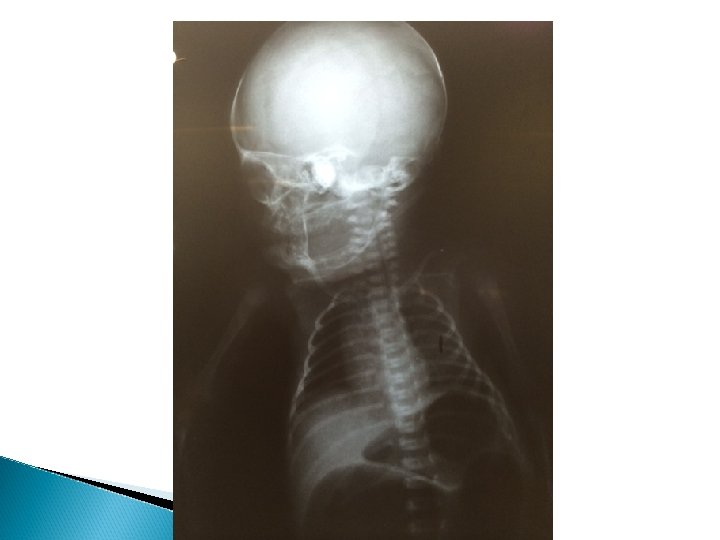

RX HMIB

Caso Clínico 2º DIH UCIN: Realizado radiografia de abdome evidenciando “duas bolhas intestinais” (descrição em prontuário) Realizado ultrassom de abdome total: “Ausência de alterações detectáveis no presente estudo” Solicitado vaga em UTIN e parecer da cirurgia pediátrica;

Atresia Intestinal Diagnóstico: A radiografia simples de abdome, em pé e deitado, pode definir o diagnóstico; A presença de duas bolhas gasosas no hemiabdome superior é indicativa de obstrução duodenal completa; poucas bolhas, de obstrução jejunal e, várias bolhas, obstrução ileal e de colo; Deve-se evitar a utilização de contraste baritado;